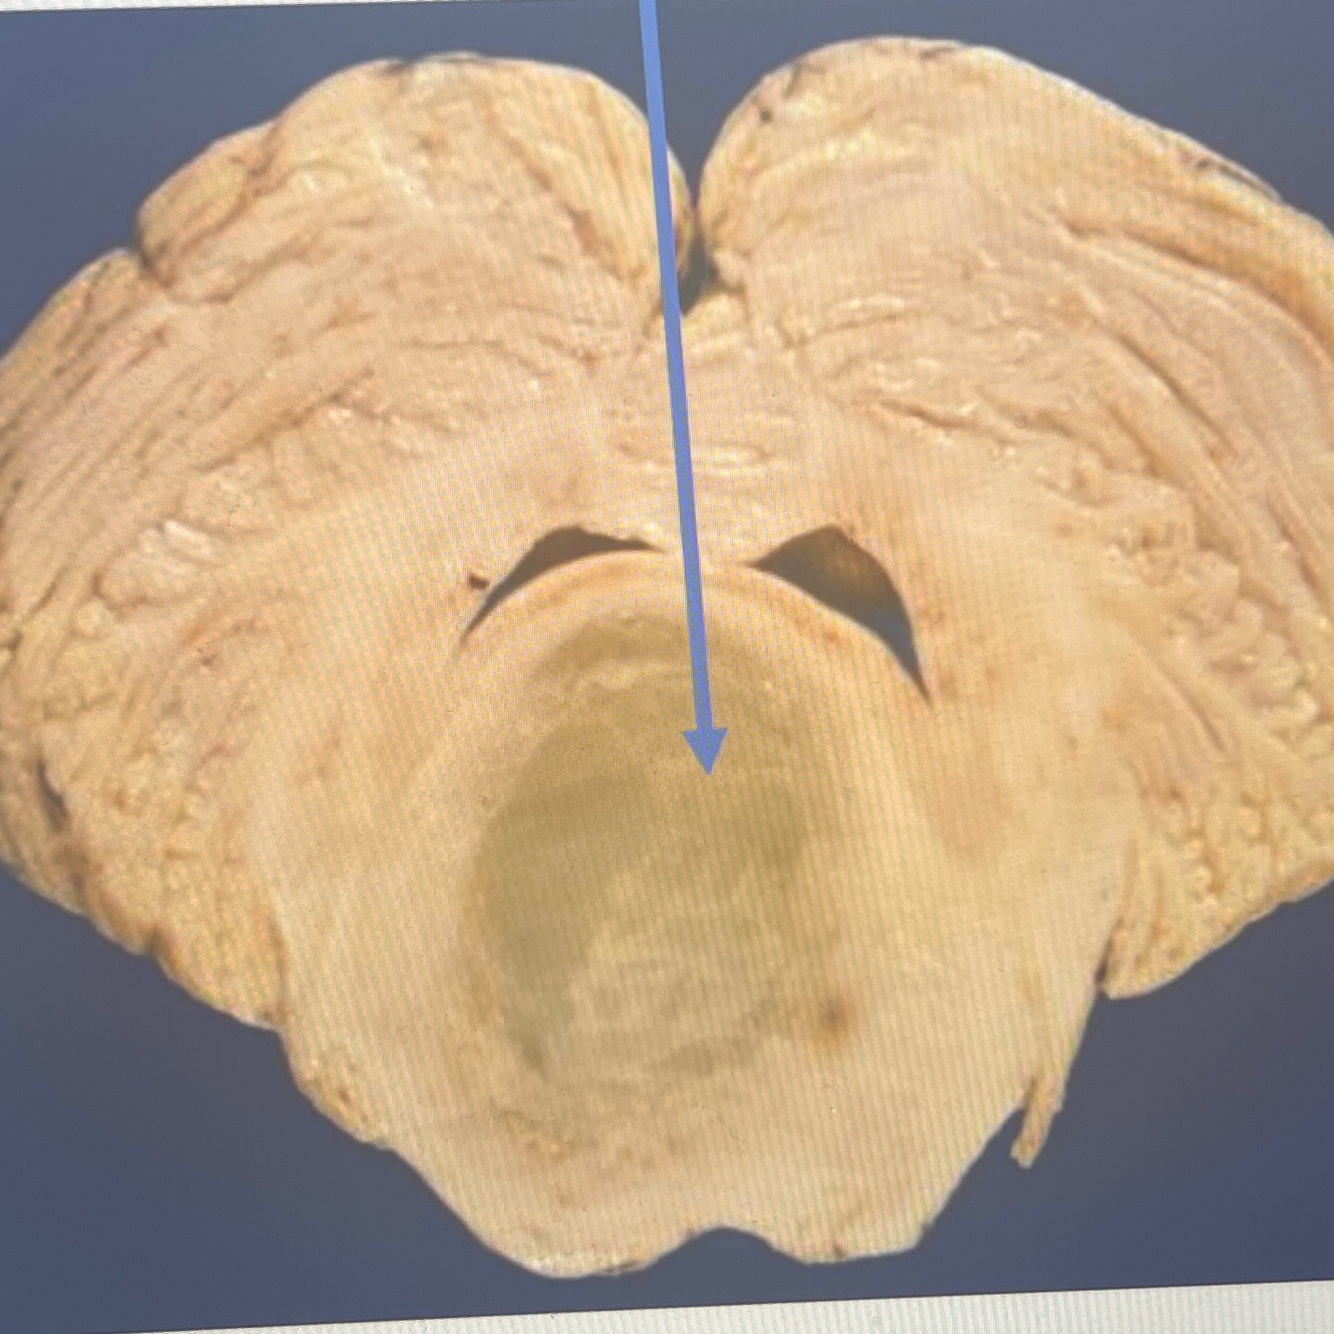

Diagnosis: intraventricular hemorrhage

Location: lateral and third ventricles

A coronal section in the brain showing a collection of blood in the subependymal region and within the lateral and third ventricles in a premature newborn

The brain parenchyma is compressed